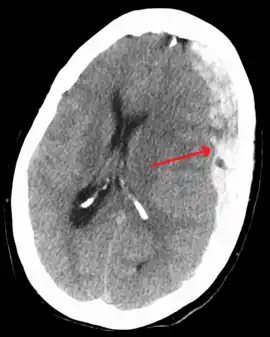

It is important that a person receive medical assessment, including a complete neurological examination, after any head trauma. A CT scan or MRI scan will usually detect significant subdural hematomas.

Subdural hematomas occur most often around the tops and sides of the frontal and parietal lobes.[3][2] They also occur in the posterior cranial fossa, and near the falx cerebri and tentorium cerebelli.[3] Unlike epidural hematomas, which cannot expand past the sutures of the skull, subdural hematomas can expand along the inside of the skull, creating a concave shape that follows the curve of the brain, stopping only at dural reflections like the tentorium cerebelli and falx cerebri.

On a CT scan, subdural hematomas are classically crescent-shaped, with a concave surface away from the skull. However, they can have a convex appearance, especially in the early stages of bleeding. This may cause difficulty in distinguishing between subdural and epidural hemorrhages. A more reliable indicator of subdural hemorrhage is its involvement of a larger portion of the cerebral hemisphere. Subdural blood can also be seen as a layering density along the tentorium cerebelli. This can be a chronic, stable process, since the feeding system is low-pressure. In such cases, subtle signs of bleeding—such as effacement of sulci or medial displacement of the junction between gray matter and white matter—may be apparent.

Fresh subdural bleeding is hyperdense, but becomes more hypodense over time due to dissolution of cellular elements. After 3–14 days, the bleeding becomes isodense with brain tissue and may therefore be missed.[20] Subsequently, it will become more hypodense than brain tissue.[21]